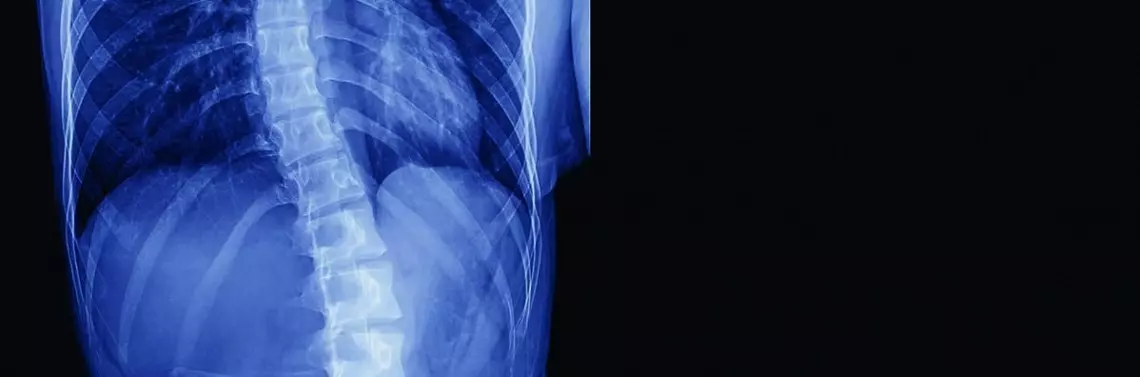

Leczenie skolioz, kifoz, lordoz z uwzględnieniem m.in. zasad metody FED

Ośrodek Specjalistycznej Fizjoterapii „BIO” Mariusz Czarnecki jako trzeci ośrodek w Polsce wprowadził w 2011 r. metodę FED. Ma on duże doświadczenie w bez- operacyjnym leczeniu skolioz, kifoz i lordoz. W niniejszym materiale przedstawiono wybrane przypadki i wyniki leczenia.